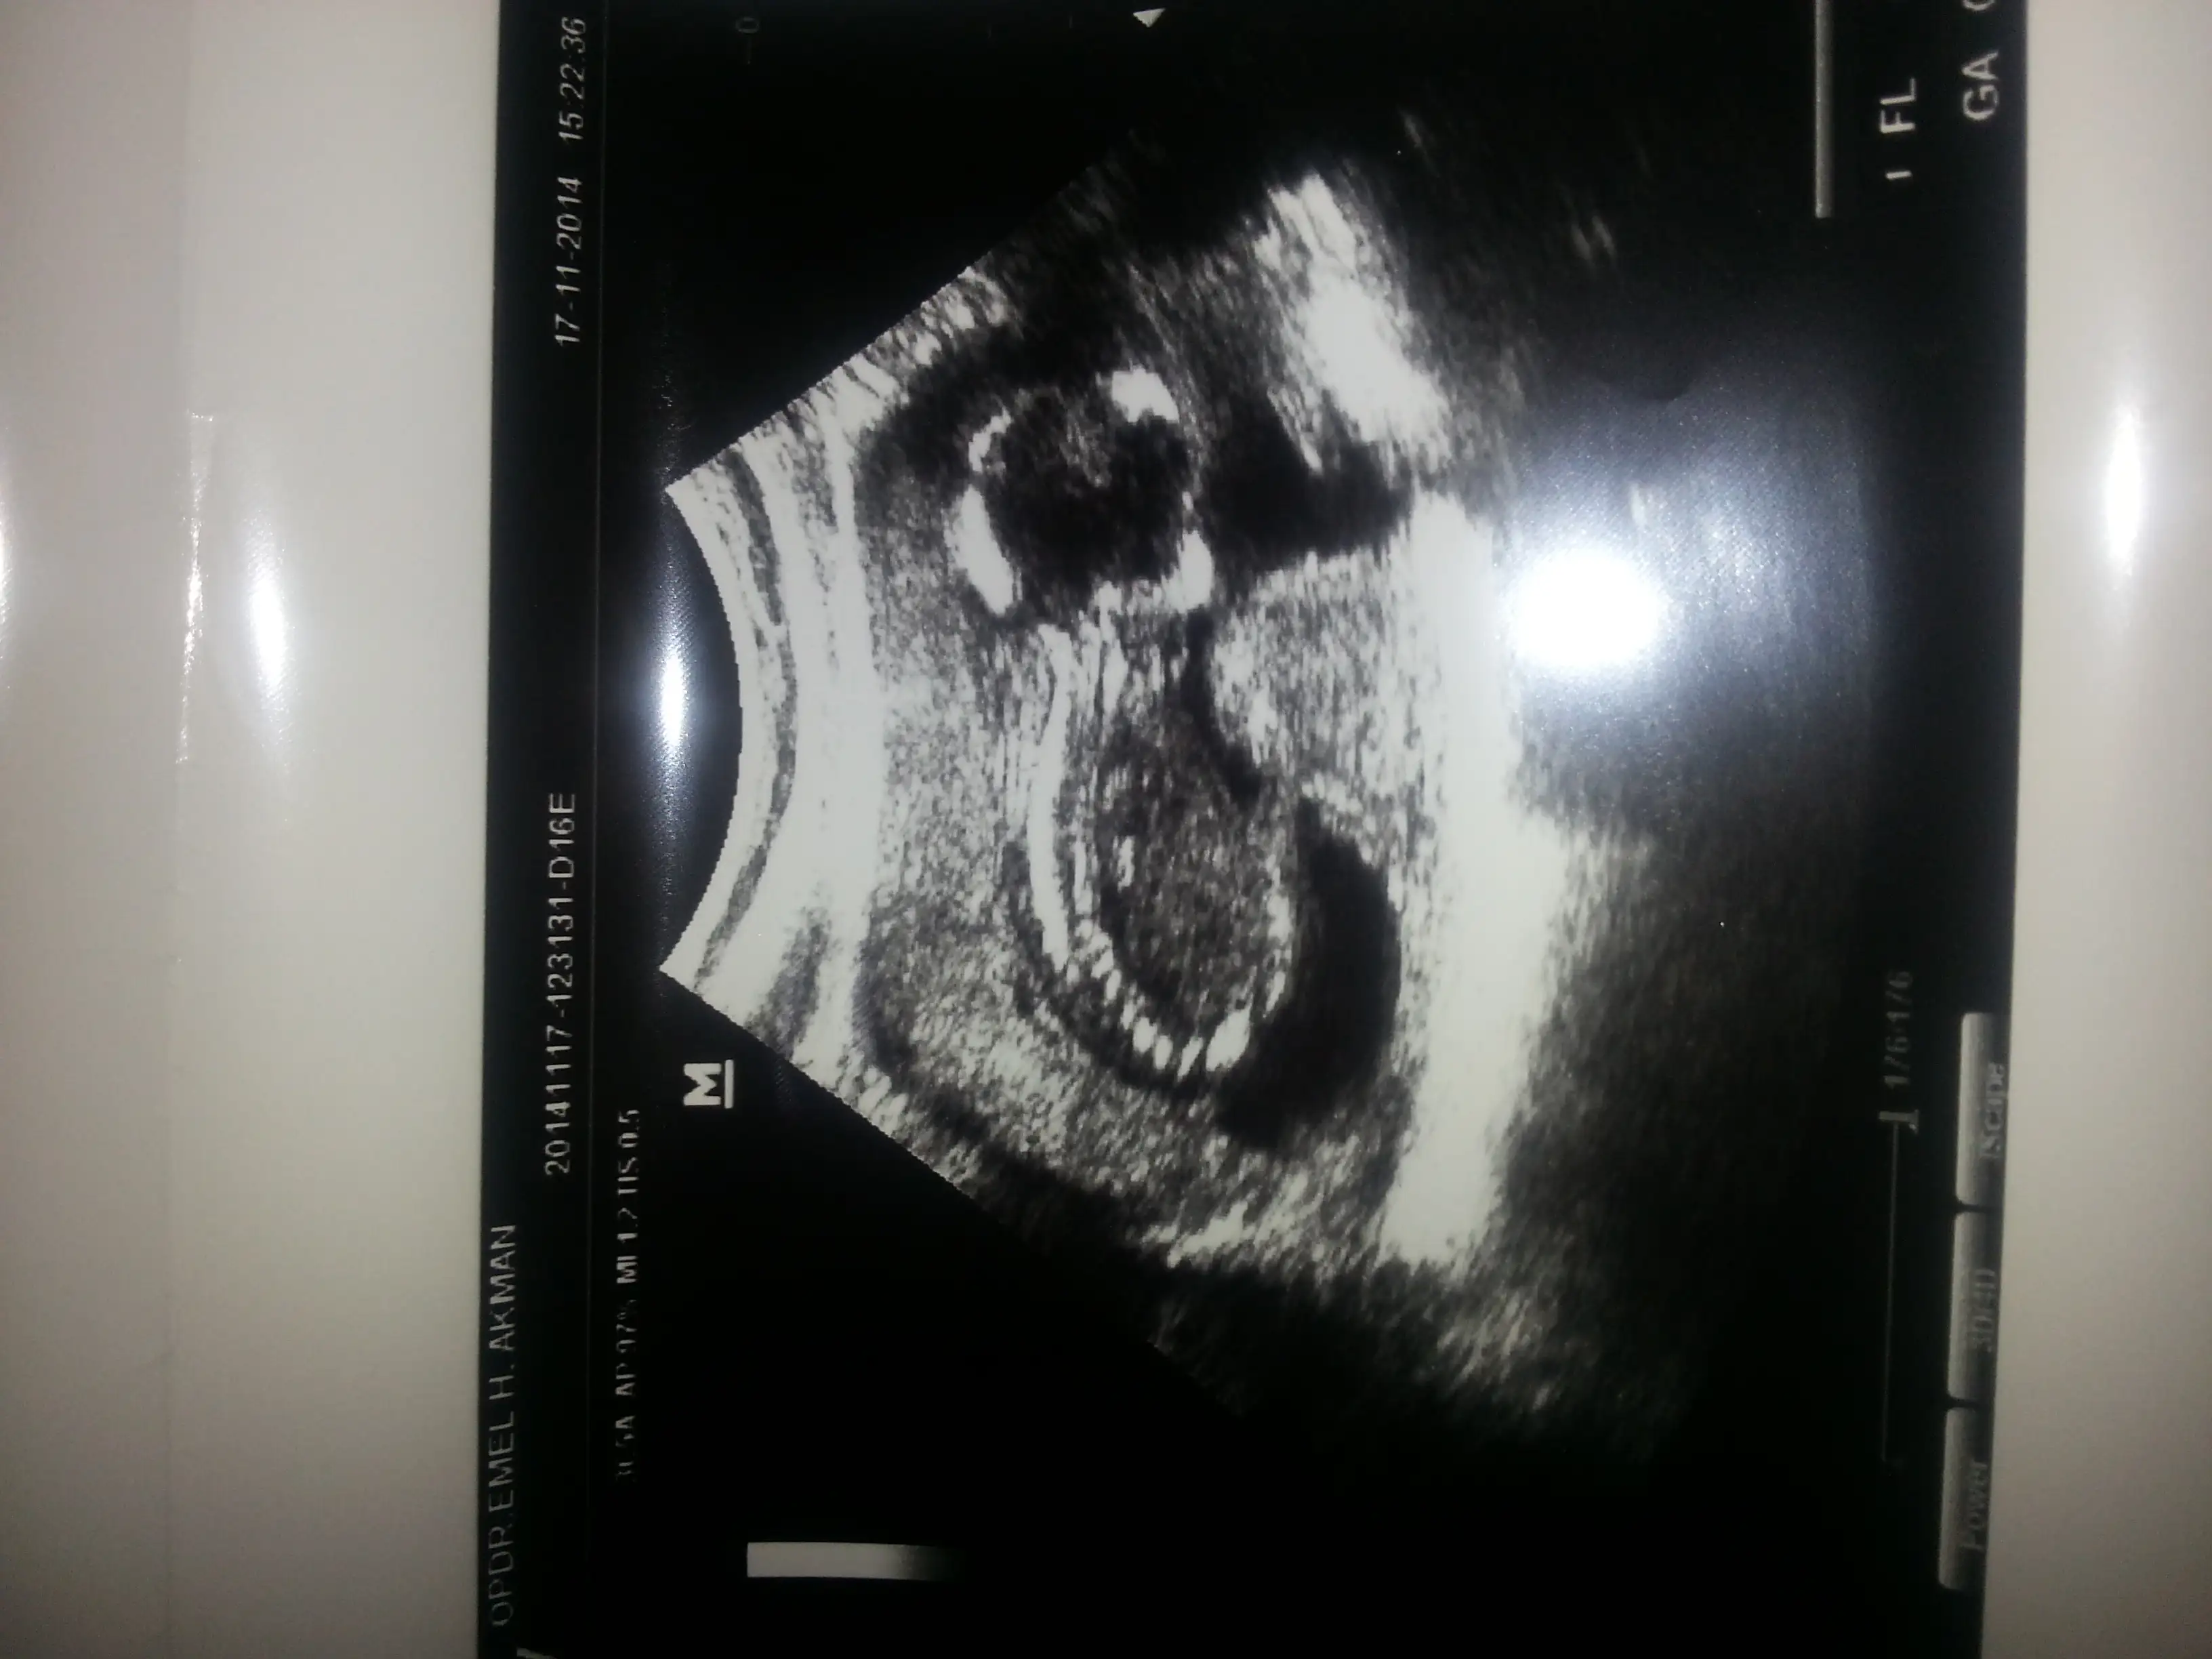

yarin bebegimle bulusuyorum loley loley loleeeeyyBekle beni kuzucumm

Ayyy guzel haberlerle gelirsin insallah tatlim kuzun da ozlemistir seni